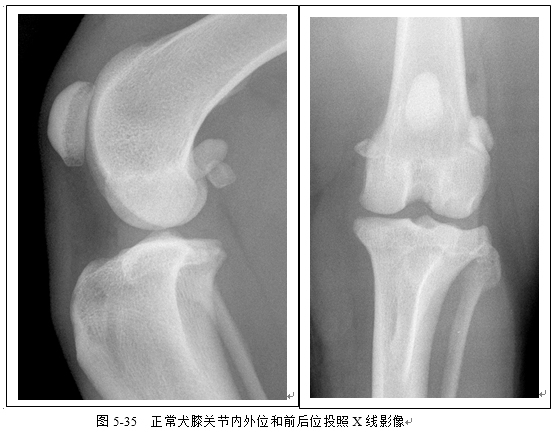

(3)识别胫腓骨、股骨、跗关节、膝关节X线影像(图5-32、5-33、5-34、5-35)。